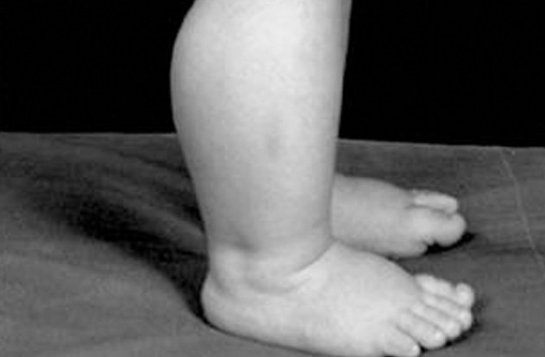

Рожденные с генетическим заболеванием, известным как синдром Марфана, имеют буквально резиновые сухожилия и связки. Мутации в гене, ответственном за производства белка фибриллин-1, приводят к тому, что тело создает соединительную ткань с нечеловеческой гибкостью. Такие люди могут скручивать тело в удивительные формы, которым позавидовал бы сам Мистер Фантастик.

Конечно, у этого подарка есть своя цена. Такие люди могут обзаводиться неестественно длинными конечностями и уродствами лица. Генетический дефект также приводит к проблемам со скелетом, нервной системой и даже сердцем, некоторые из которых могут быть фатальными.